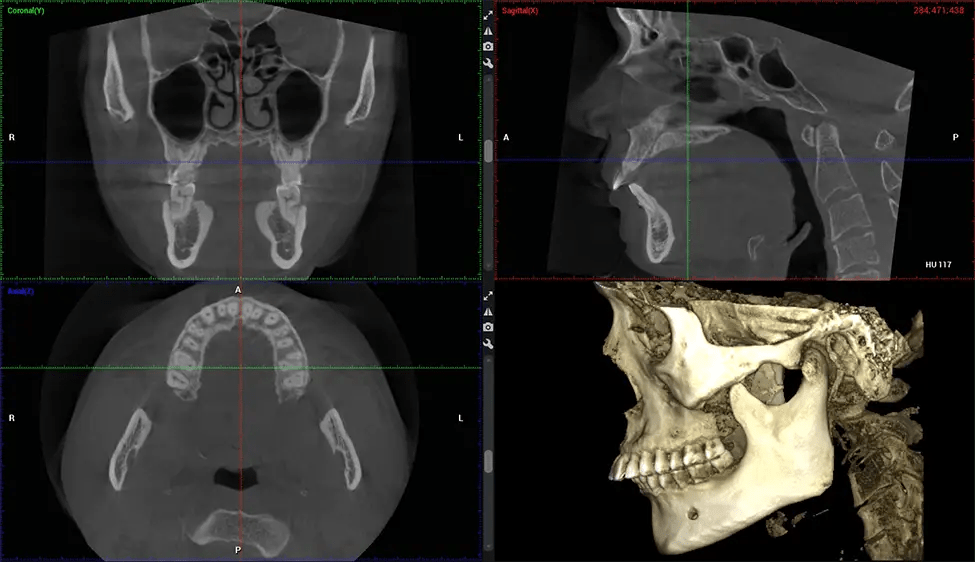

Cone Beam Computed Tomography (CBCT) is an advanced imaging technique used in dentistry and maxillofacial surgery to obtain detailed 3D images of the oral and maxillofacial structures. At Dr G Dental Studio, our CBCT scanners utilize a cone-shaped X-ray beam and a specialized detector to capture images from different angles. A computer then combines these images to create a 3D representation of the patient’s oral anatomy.

This 3D scan, called cone beam computed tomography, gives your dentist a more complete image of your oral anatomy and disease processes than a traditional X-ray. Unlike conventional X-rays, which capture a 2D image of your mouth from various angles, a 3D scan takes multiple digital X-rays for one image. It provides a complete view of your jaw, teeth, nerves, and soft tissues. This enhanced view allows dentists to detect minor issues not visible in traditional 2D scans, such as impacted wisdom teeth or bone fractures in the sinus cavity.

After the scanning process, the captured X-ray images are processed by the CBCT software, which applies algorithms to reconstruct a detailed 3D image of the scanned area. The software compiles these individual X-ray images and creates a digital 3D representation of the patient’s anatomy. The reconstructed 3D CBCT image can be viewed and analyzed by the dentist or radiologist. This image can be manipulated, rotated, and zoomed in or out to examine specific structures and evaluate the patient’s condition.